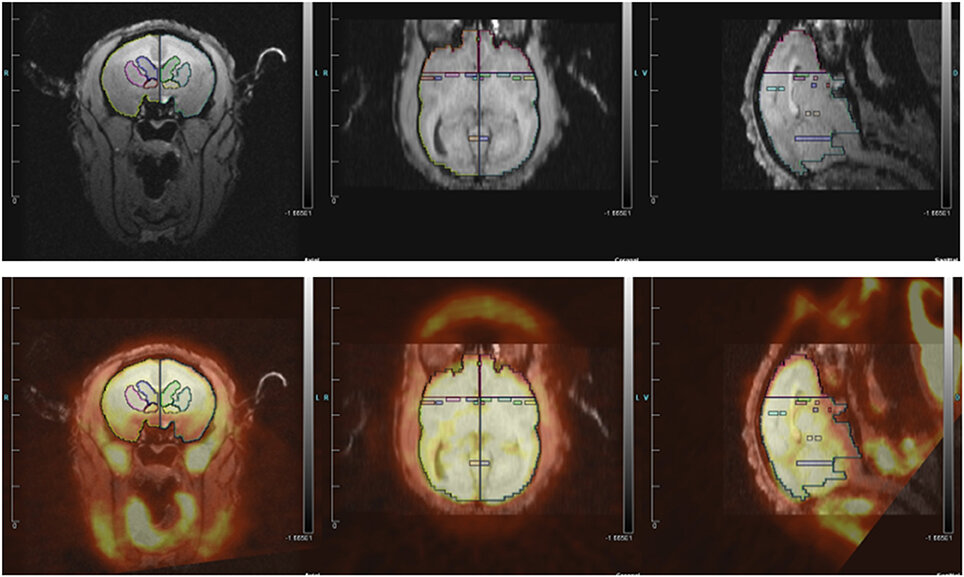

Вверху: МРТ зон интереса исследователей у обезьянок. Внизу: наложение ПЭТ-изображений обезьянок в состоянии ревности

Исследователи вызывали состояние ревности у самцов, размещая в поле зрения их партнёршу с незнакомым «мужчиной». Для сравнения на другой день эксперимент повторяли с чужой самкой и самцом. После 30 минут просмотра, в течение которых поведение самцов снимали на камеру, учёные провели сканирование мозга посредством позитронно-эмиссионной томографии, чтобы увидеть активные области. Они также измерили уровни различных гормонов в крови.

Исследователи обнаружили, что в состоянии ревности мозг обезьян показал повышенную активность в поясной коре – области, связанной с социальной болью (которая бывает, например, при расставании или одиночестве). Также активность повысилась в латеральной перегородке, отвечающей за эмоциональные процессы и уровень стресса. У ревнивых мужчин проявились и гормональные изменения: значительно повысился уровень тестостерона и кортизола.